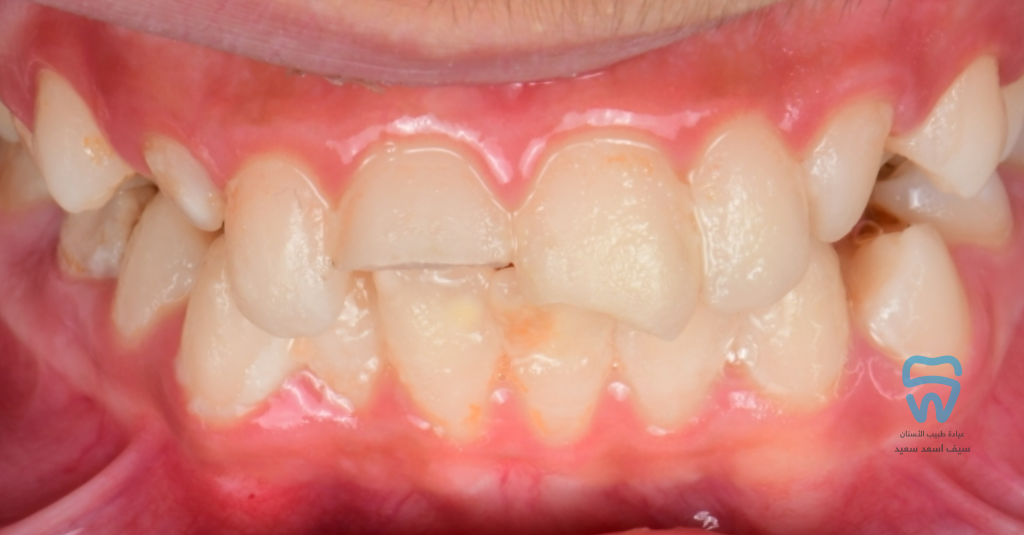

patient came with 2 fractured upper centrals

Complicated crown fracture